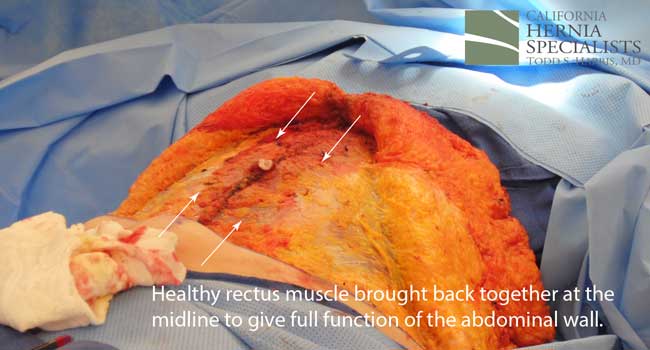

The more complete approach would be to bring healthy muscle together at the mid line. Only after the muscle is repaired completely, can a mesh be used to SUPPORT the muscle repair. Meshes should not be considered a bridge from healthy muscle to healthy muscle. Instead mesh should be used as a reinforcement of a correct hernia repair.

This technique requires more surgical time, recovery time, and usually several days in the hospital. However, this patient chose to proceed with the open hernia repair. Below are some of the pictures from his surgery as well as post operative CT scan image and photos of the patient.

Because this patient had failed two prior surgeries, we performed a complex open hernia repair on him. This repair included a technique called ‘component separation’, where the oblique muscles on the sides of the abdomen, are partially released, or cut, to allow the rectus muscles to be pulled back together in the middle of the abdomen.

Since the abdominal muscles were weakened, we placed a sheet of biologic mesh under the muscle in the middle at the area of the hernia hole, closed the muscle over this mesh, then placed another mesh on top of the muscles which were closed. This provided him with three layers of repair.

The CAT scan image below compares the patient before surgery, and then after surgery when the muscle has been pulled back together and the hernia has been repaired.